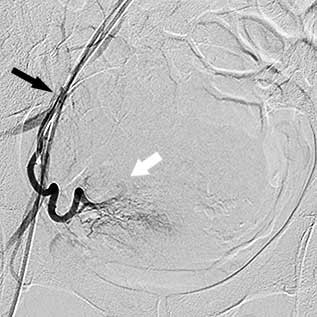

Ендоваскулярний хірург робить прокол шкіри голкою в паховій складці або руці та, потрапивши в артерію, вводить туди тонку (1,5–2 мм), спеціально зігнуту трубку — катетер. Оскільки процедура малоболісна, використовується лише місцева анестезія, яку доповнюють препаратами для легкого медикаментозного сну. Хірург під рентгенівським контролем проводить катетер артеріями до матки — спеціальна апаратура дозволяє стежити за переміщенням катетера всередині тіла. Катетер по черзі підводиться до правої та лівої маткової артерії. Далі виконується артеріограма — введення в маткову артерію спеціальної контрастної речовини, видимої під рентгеном, що дозволяє "побачити" фіброміому і підтвердити правильне розташування катетера.

Права маткова артерія:

чорна стрілка - катетер, білі стрілки -

розширені артерії вузла

Ліва маткова артерія: